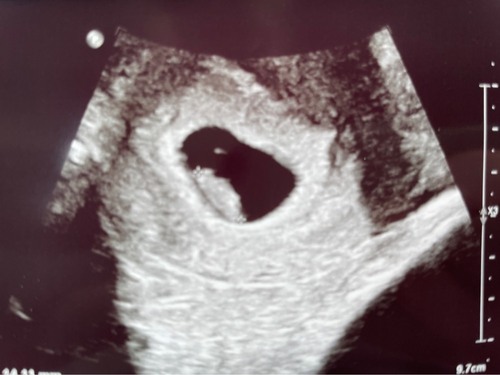

Ramzi is (weliswaar niet betrouwbaar maar wel leuk) een theorie die TOT 8 weken gebruikt kan worden door te kijken waar de placenta ontwikkeld.

Deze foto's geven alleen niet voldoende beeld van de baarmoeder om het te kunnen zien naar mijn mening. Heeeeeeeel misschien iets eerdee rechts en dan zou het met inwendige echo een jongetje zijn volgens de theorie.

Als je Ramzi moet geloven ontwikkeld de placenta vaak rond de vrucht dus dat zou bij jou links zijn. Je hebt een uitwendige echo gehad dus de ramzi zou dan voor nu zeggen een jongen, geloof ik. 😅

Wat denken jullie? 6+3 uitwendige echo, kwam er zelf niet helemaal uit, bij mijn dochter klopte het wel en de nub ook. Ben heel benieuwd nu 🥰

Het dooier zakje leek rechts te zitten toen ze inzoomde